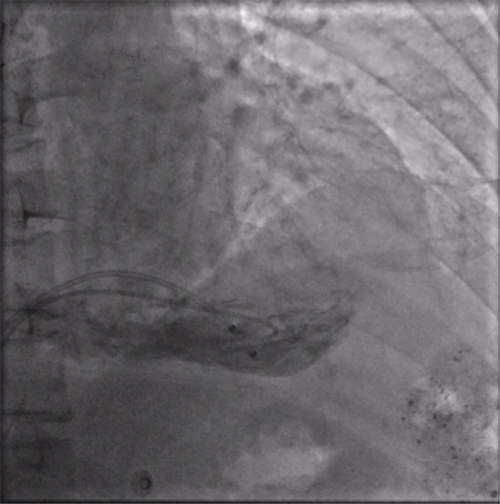

右室猪尾导管造影